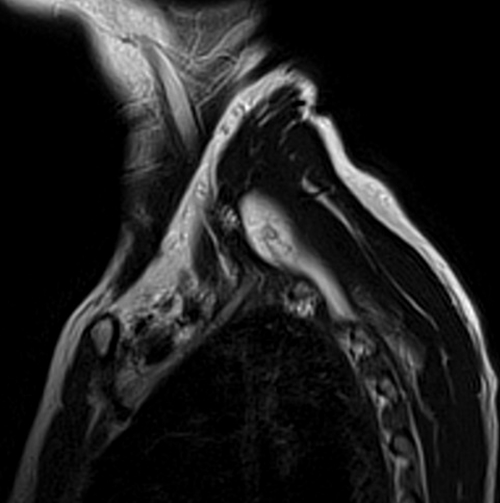

MRI brachial plexus anatomy free MRI coronal cross sectional anatomy of the brachial plexus Mri Anatomy Brachial Plexus to localize plexus lesions detected on mr imaging, knowledge of the anatomy of the plexus and the relationship of the plexus to adjacent muscles,. It provides clear structural analysis of the brachial plexus, its. mri of the brachial plexus is used to provide a causal diagnosis for brachial plexopathies. the brachial plexus (bp) provides sensory and motor. Mri Anatomy Brachial Plexus.